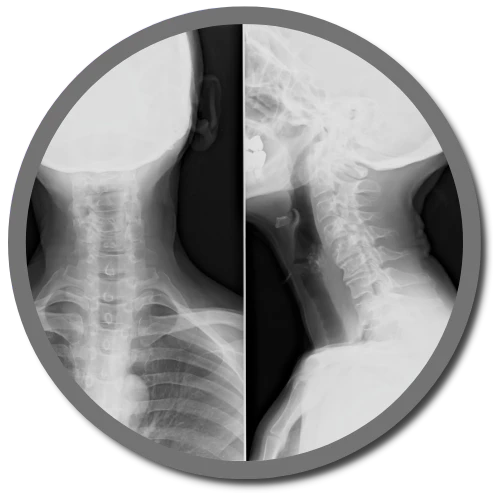

The Gonstead Technique relies on five essential components: Visualization, Instrumentation, Palpation, X-Ray, and patient symptoms. By integrating these elements, we can pinpoint the precise location that requires adjustment. When all these factors align, we can provide the patient with a specific and effective adjustment. Specificity is the key, as Dr. Gonstead emphasized that three adjustments on the wrong vertebral segment could lead to a Subluxation, highlighting the importance of precision.

Dr. Gonstead's Level Disc Theory asserts that "anatomically and physiologically normal discs promote optimum vertebral alignment." This is evidenced when the vertical height of a vertebral couple is uniform around 360 degrees, with the vertebral bodies properly aligned. This alignment, known as "Parallel Discs," ensures even weight distribution, adequate nutrient flow, and optimal joint function and movement within the spine.